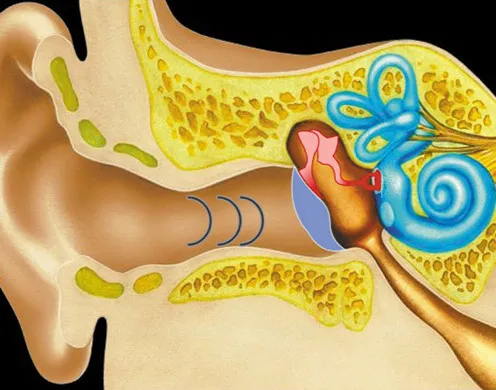

Dementsprechend finden Sie hier auch eine facettenreiche Mischung der bei uns angebotenen Produkte. Auch einen Fokus auf die Biologie des Menschen legt der Bereich der Neurophysiologie. Die bei uns erhältlichen Themenpakete vermitteln anschaulich die Funktion des menschlichen Nervensystems beziehungsweise Gehirns. Die Ökologie bildet einen weiteren klassischen und in unserer Zeit ebenso relevanten Wissenschaftsbereich der Biologie. Vom Klimawandel über Lebenskreisläufe bis hin zum Thema Recycling dreht sich bei diesen Bildungsmedien für Biologie alles um die Umwelt.